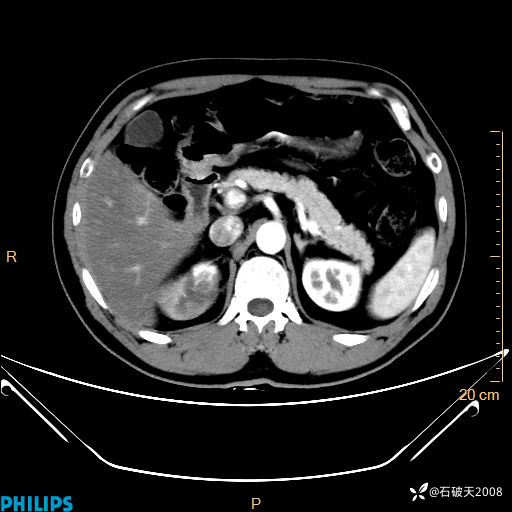

增强轴位